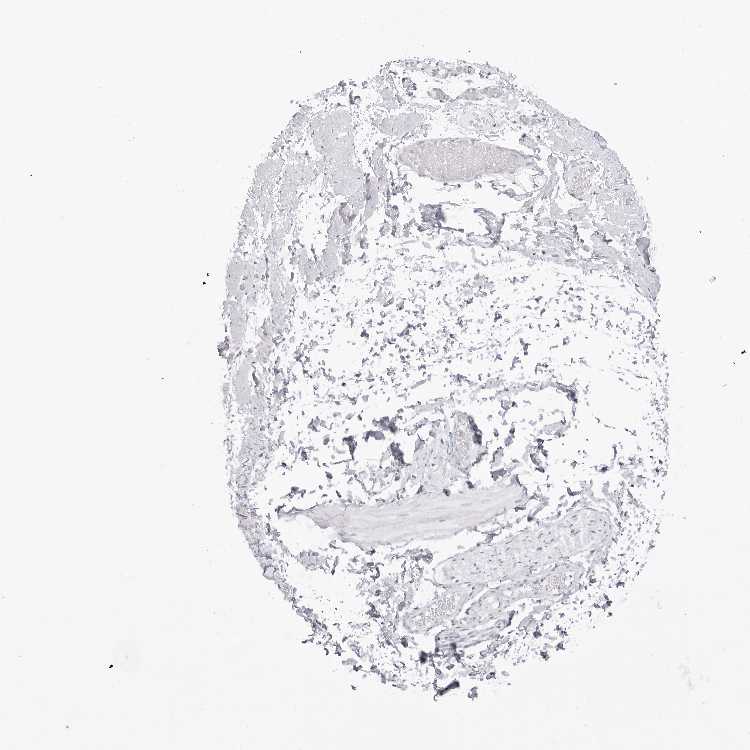

SOFT TISSUE 1 - Antibody stainingi

Antibody staining in the annotated cell types in the current human tissue is reported as not detected, low, medium, or high, based on conventional immunohistochemistry profiling in selected tissues. This score is based on the combination of the staining intensity and fraction of stained cells.

Each image is clickable and will lead to virtual microscopy that enables deeper exploration of all samples and also displays staining intensity scores, fraction scores and subcellular localization as well as patient and tissue information for each sample.

Antibody HPA028136Antibody HPA030518Antibody HPA030520

Chondrocytes Not detectedNot detectedHigh

Fibroblasts Not detectedNot detectedNot detected

Peripheral nerve Not detectedNot detectedMedium